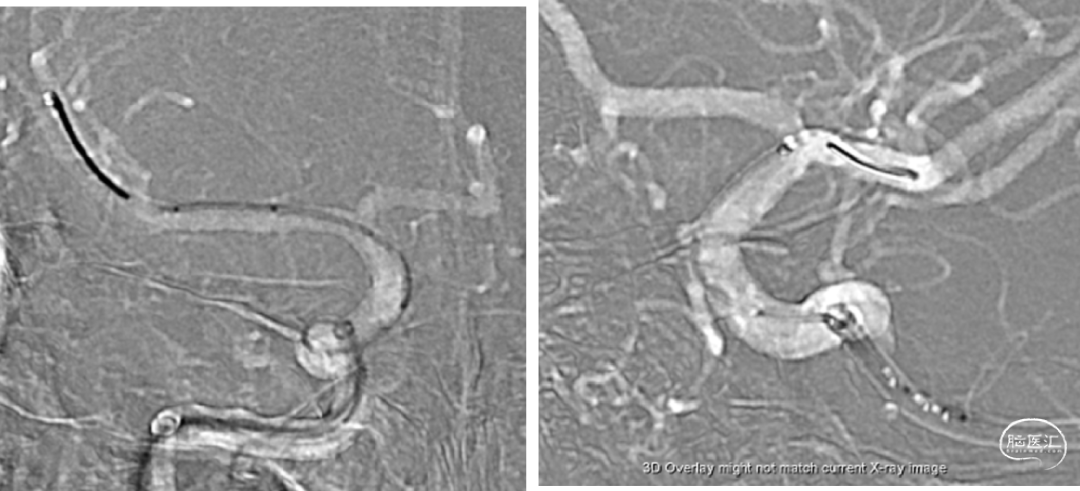

术后即刻造影